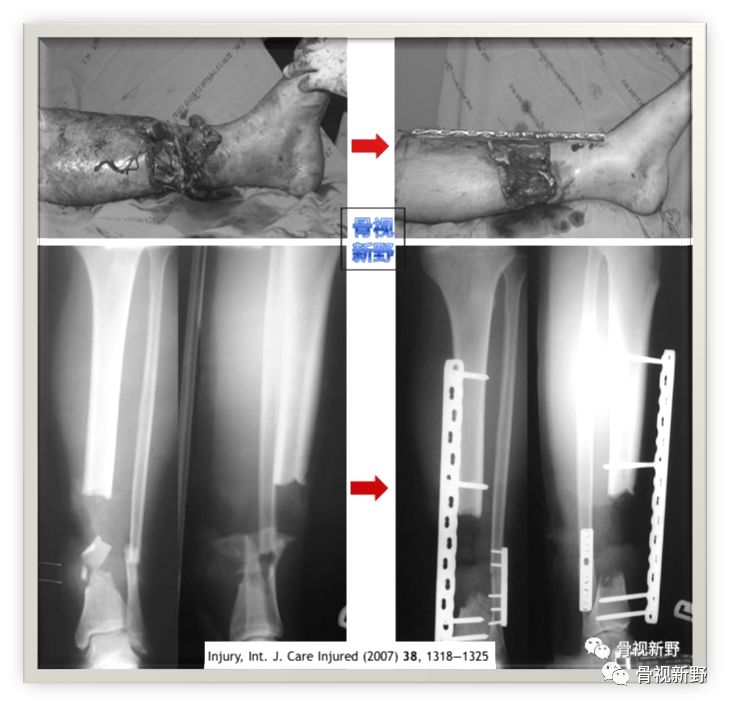

2003年,Rene K.Marti团队再次报道了将AO标准钢板作为外固定架用于开放性骨折以及骨感染性骨不连的固定病例31例,也取得了较好的疗效。

Cases